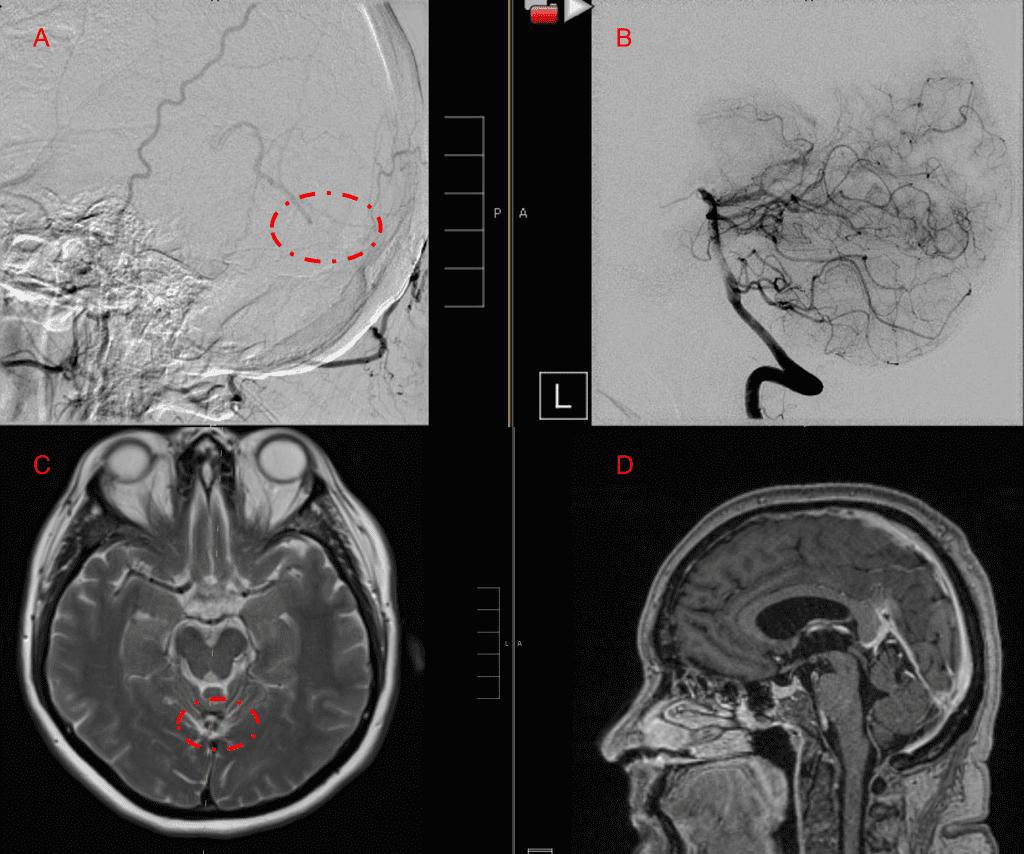

A 55-year-old woman presented with acute onset of severe headache, and possible witnessed seizure. Imaging confirmed intraventricular hemorrhage primarily focused within the fourth ventricle with diffuse subarachnoid hemorrhage within the posterior fossa and along the tentorium as observed on non-contrast CT and MRI of the Brain (Figure 1).

Figure 1. A and B) Non-Contrast CT Axial and Coronal demonstrate large, ruptured Varix/Aneurysm along the Incisura of the posterior fossa which appears to have mixed hemorrhagic components and enhancement on MRI T2 and post contrast imaging (C and D).